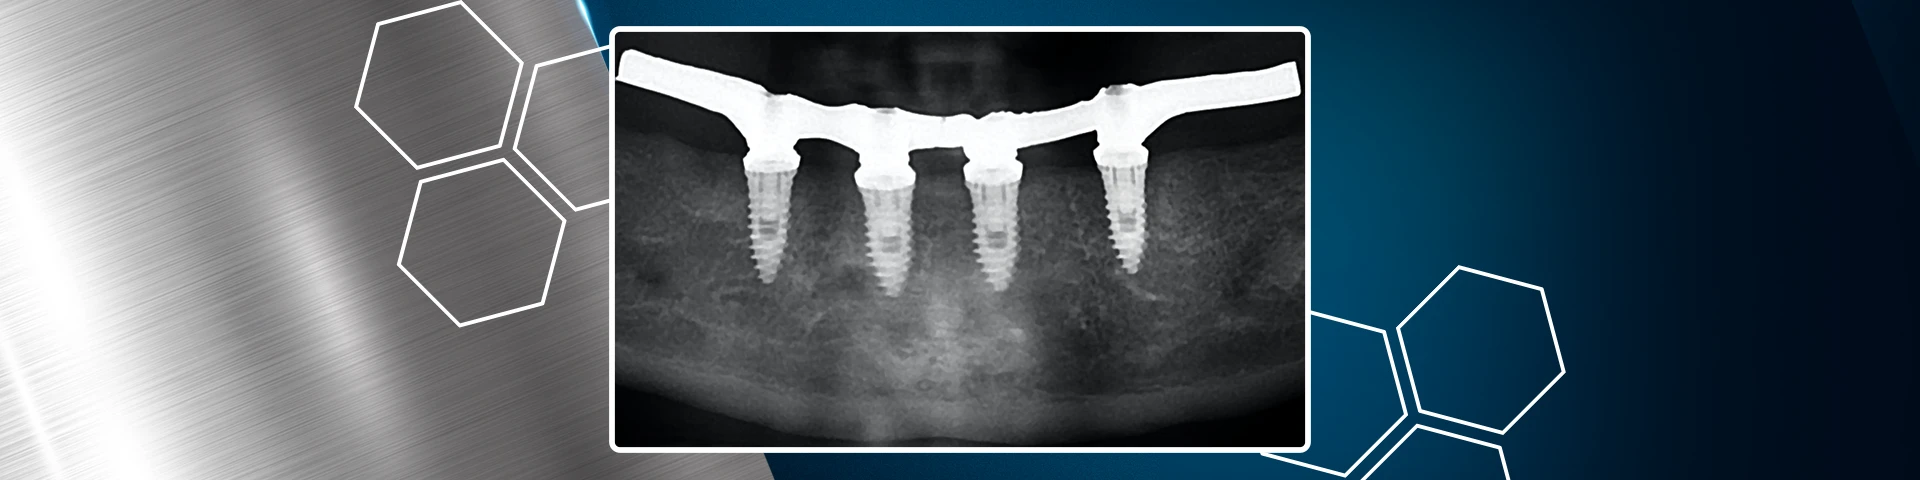

Manutenção óssea alveolar com Nanosynt e implantes dentários hexágono externo Vezza HE

Autores: Diego Bazan e Fábio Lorenzoni Gênero e idade do paciente: Paciente do sexo masculino, 57 anos de idade. Queixa Principal Necessidade de exodontias e implantes dentários Avaliação inicial Após anamnese detalhada o paciente apresentava um bom estado de saúde geral. Durante o exame clínico e radiográfico foi detectado dente 46 com fratura radicular e […]